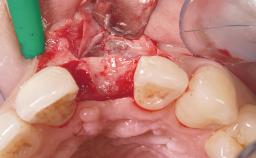

Late Flapless Placement of an Implant in a Maxillary Left Central Incisor Site

A 39-year-old male patient presented with a chief complaint of discomfort and gingival discoloration around his maxillary left central incisor. He was in good general health and was a non-smoker. His past dental history was significant because of the traumatic fracture of tooth 21 in a sporting accident at age 13. Initial dental treatment included endodontic therapy and a full-coverage restoration. The patient became symptomatic 5 years later, when structural failure of the tooth resulted in the dislodgment of the crown. Endodontic retreatment, apical surgery, and post-and-core restoration were performed.

Bone Augmentation Horizontal|Staged